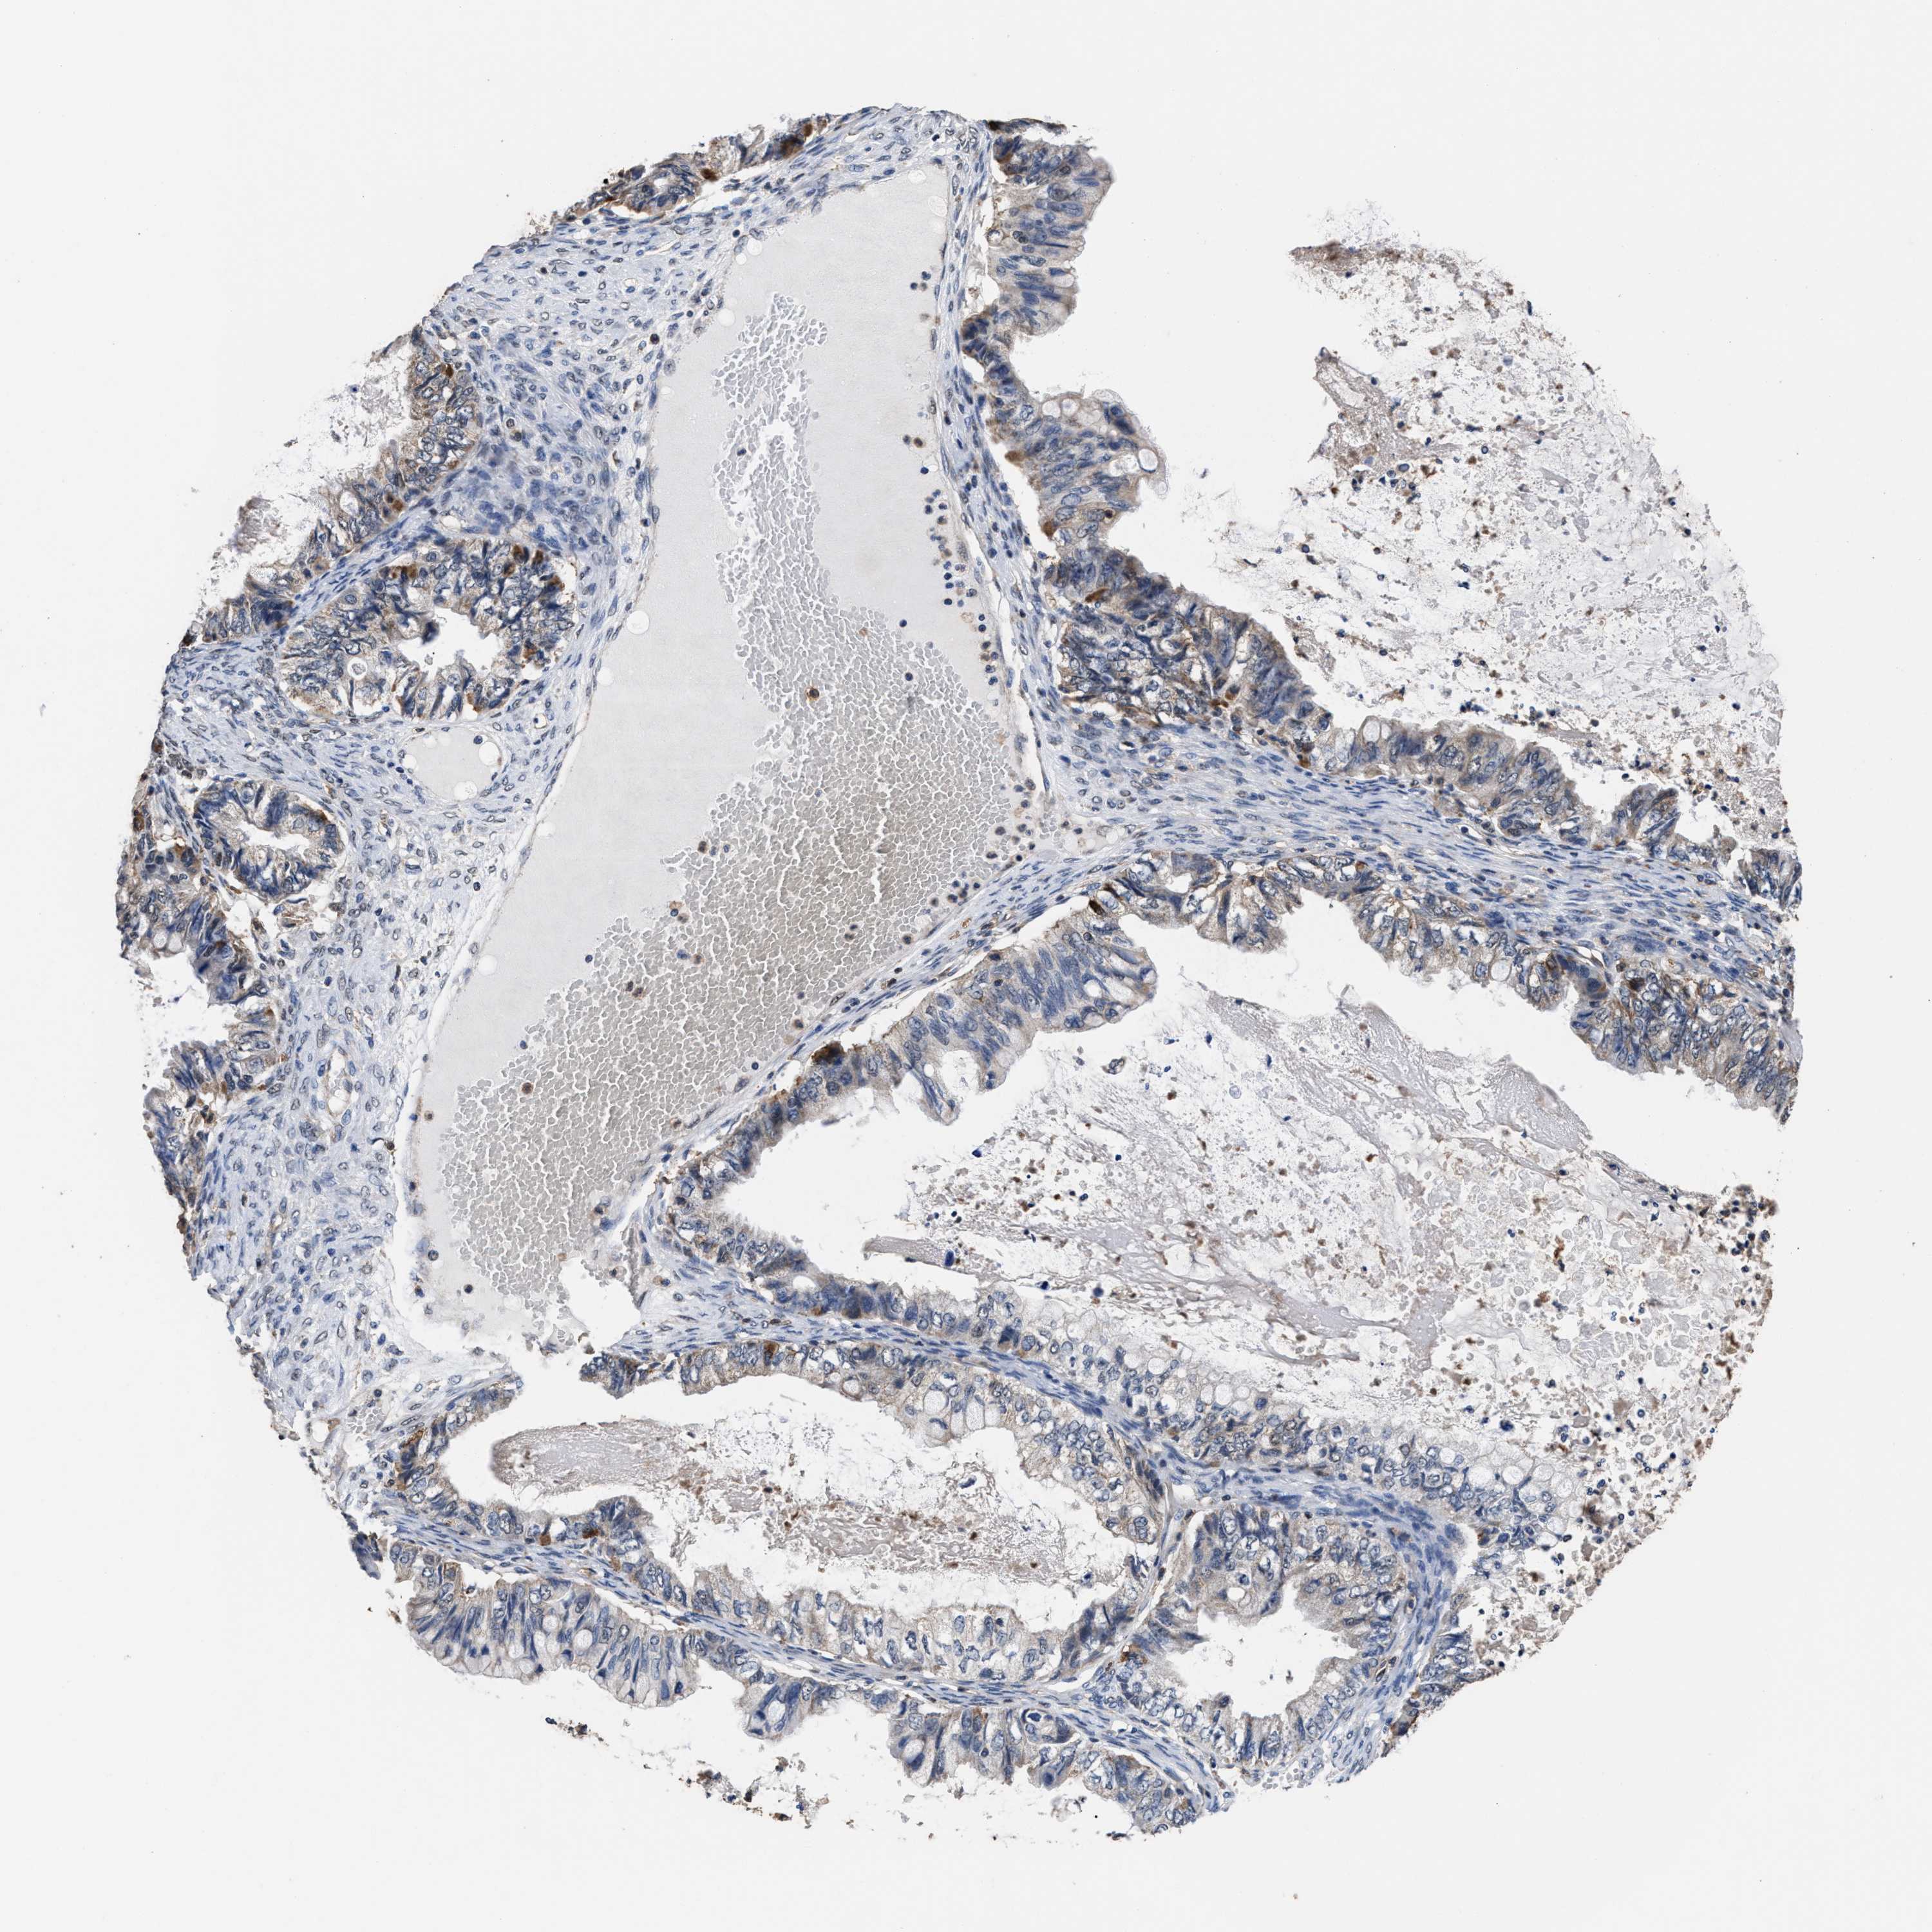

OVARIAN CANCER - Protein expressioni

A mouse-over function shows sample information and annotation data. Click on an image to view it in a full screen mode. Samples can be filtered based on level of antibody staining by selecting one or several of the following categories: high, medium, low and not detected. The assay and annotation is described here.

Note that samples used for immunohistochemistry by the Human Protein Atlas do not correspond to samples in the TCGA dataset.

Antibody stainingi

Antibody staining in the annotated cell types in the current human tissue is reported as not detected, low, medium, or high, based on conventional immunohistochemistry profiling in selected tissues. This score is based on the combination of the staining intensity and fraction of stained cells.

Each image is clickable and will lead to virtual microscopy that enables deeper exploration of all samples and also displays staining intensity scores, fraction scores and subcellular localization as well as patient and tissue information for each sample.

HPA022434

HPA022953

HPA022959

HPA028758

CAB007783

Staining

High

Medium

Low

Not detected

Intensity

Strong

Moderate

Weak

Negative

Quantity

>75%

75%-25%

<25%

None

Location

Nuclear

Cytoplasmic/membranous

Cytoplasmic/membranous,nuclear

Cystadenocarcinoma, serous, NOS

Carcinoma, endometroid

Cystadenocarcinoma, mucinous, NOS

Carcinoma, NOS